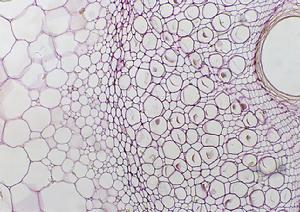

(4)骨病變:主要表現為骨質疏鬆及骨質吸收,以指骨撓側骨膜、顱骨、牙 槽骨板為好發部位。病程長或嚴重時可發展至囊性纖維性骨炎、長骨棕色瘤與骨囊腫。易發生病理性骨折。典型骨病變為囊 狀纖維性骨炎;經皮骨活檢典型者可見皮質寬度變窄,骨形成和骨吸收表面增加。X線可見骨骼脫礦質現象,指骨橈側骨膜 下吸收,長骨棕色瘤與骨囊腫,顱骨蟲蝕樣陰影,牙齒硬板層消失。晚期纖維囊性骨炎,可出現骨骼畸形和病理性骨折,致 患者行走困難,甚至臥床不起。部分患者出現骨囊腫,表現為局部骨質隆起。

原發性甲旁亢是甲狀旁腺腺瘤、增生 肥大或腺癌所引起PTH分泌過多。由於甲狀旁腺激素分泌過多,鈣自骨動員至血循環,引起血鈣過高;同時腎小管對無機磷 再吸收減少,尿磷排出增多、血磷下降、血鈣升高不能抑制甲狀旁腺。持續增多的PTH作用,引起廣泛骨質吸收脫鈣等改變 。骨基質分解,黏蛋白、羥脯氨酸等代謝產物自尿排泄增多,形成腎結石或腎鈣鹽沉著症(nephrocalcinosis),加上繼發性 感染等因素,腎功能遭受嚴重損害。當腎功能不全時,磷酸鹽不能充分排出、血磷濃度反見回升,而血鈣則可降低,又可刺 激甲狀旁腺分泌,這稱繼發性甲狀旁腺功能亢進。因血鈣過高致多量鈣自尿排出,致使腎實質鈣鹽沉積,尿結石發生,發生 率在60%~90%。臨床上有腎絞痛、血尿和繼發尿路感染,還有尿頻、尿急和尿痛等症狀。本病所致的尿結石的特點為多發性 、反覆發作性和雙側性;結石又有逐漸增多、增大等活動現象。凡泌尿系統結石病人血鈣超過2.62mmol/L均應進一步檢查確 定是否為甲狀旁腺功能亢進引起的腎結石。